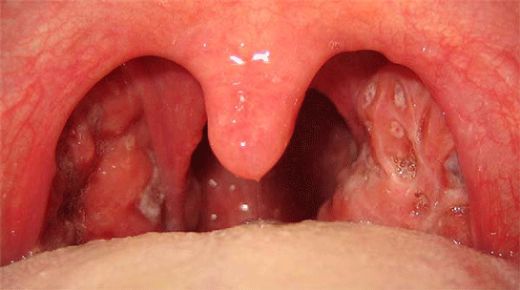

Kronik bademcik iltihabı, genellikle tekrarlayan bademcik enfeksiyonları sonucunda ortaya çıkan ve bademciklerin sürekli iltihaplanmasıyla karakterize edilen bir durumdur. Bu durum, bireylerin yaşam kalitesini olumsuz etkileyebilir. Aşağıda, kronik bademciğin belirtileri, nedenleri ve tedavi yöntemleri detaylı bir şekilde ele alınacaktır. 1. Kronik Bademcik Belirtileri Kronik bademcik iltihabı yaşayan kişilerde gözlemlenen belirtiler şunlardır:

Kronik bademcik iltihabının belirtilerini yaşayan biri olarak, sık sık boğaz ağrısı ve kötü nefes kokusu yaşıyorum. Büyümüş ve deforme olmuş bademciklerim de var. Bu belirtilerle sık sık karşılaşan biri olarak, boğaz enfeksiyonlarımın kronik bademcik iltihabından kaynaklanıyor olabileceğini düşünüyorum. Tedavi için hangi adımları atmam gerek?